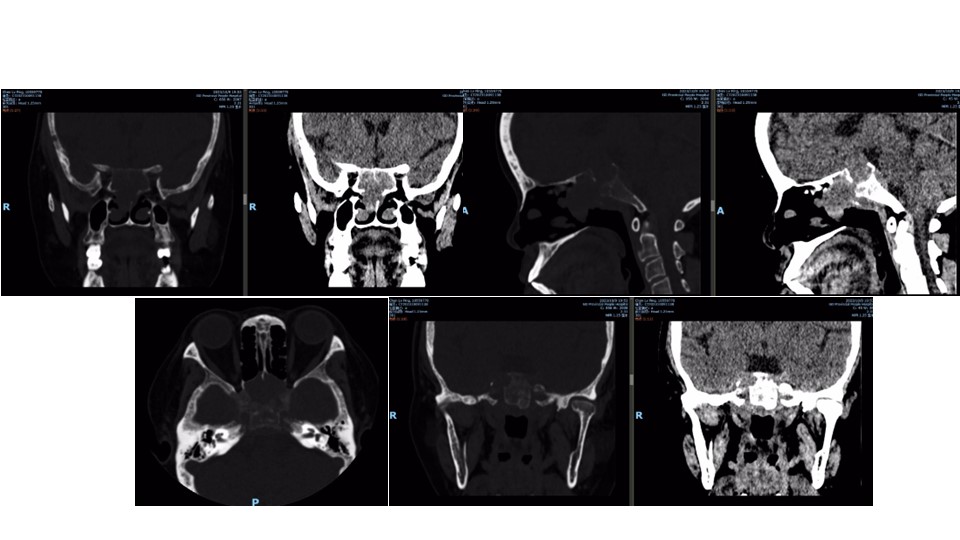

手术视频:可见广泛的骨侵袭,鼻窦、双侧颈内动脉斜坡段、破裂孔、斜坡等骨质均破坏

垂体瘤发生骨侵袭后,化疗和放疗的作用均不敏感,手术切除是目前最有效的方式,但骨侵袭也给手术造成了很多的困难,特别是存在广泛骨侵袭的垂体瘤,来自天坛医院的一组107发生骨侵袭的垂体瘤患者,全切除率低至24.3%,而且3年的复发率高达45.3%,10年的复发率几乎100%(97.5%),而且骨侵袭程度越高,手术效果越差。而对于未能全切的患者采取什么样的有效治疗方式,目前尚无定论。另外需要关注的是,发生骨侵袭,特别是颈内动脉周围骨质侵袭的,要注意颈内动脉的损伤,同样的来自天坛医院的研究显示,术中3个患者发生了颈内动脉损伤,其中一例死亡,因此,对于有广泛骨侵袭的垂体瘤患者,手术必须要格外重视,否则可能引起灾难性的后果。本例患者术中可以看到斜坡段颈内动脉、破裂孔段颈内动脉,甚至平时经鼻蝶入路难以显露的岩骨段颈内动脉亦基本裸露,同时需要在裸露的颈内动脉周围进行操作,非常容易发生损伤,因此必须高度重视。